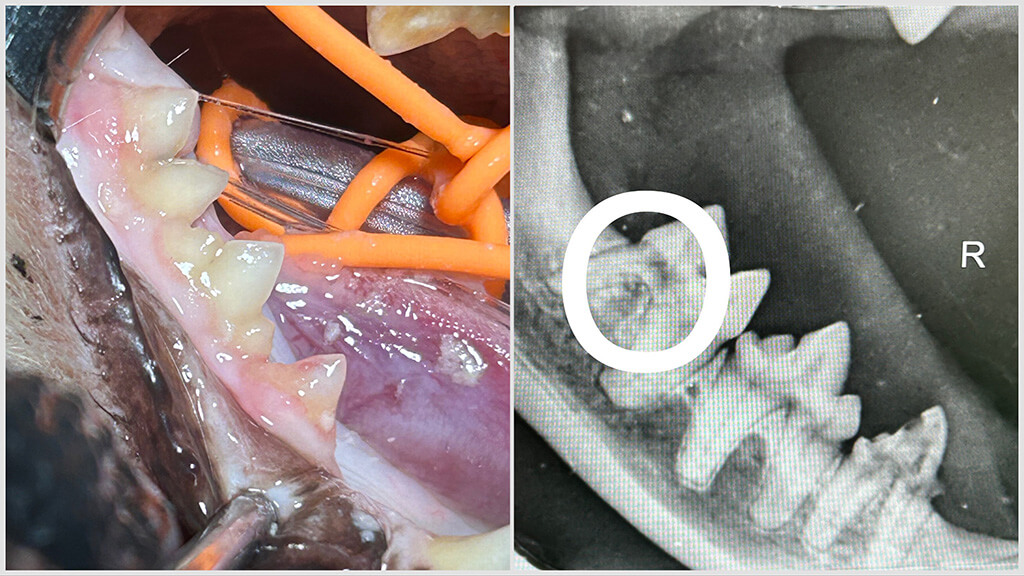

Mit unseren modernen Geräten können wir eine professionelle Zahnreinigung mit Ultraschall und anschließender Politur durchführen. Zähne, welche aufgrund ihrer Schädigung nicht erhalten werden können, werden entfernt. Oftmals kann man die Schädigung erst durch ein Zahnröntgen feststellen, daher gehört das Röntgen bei uns zur Routine. Diese gründliche Behandlung erfordert ein wenig Zeit und wird von Tieren ohne Narkose nicht geduldet. Daher vereinbaren wir mit Ihnen Termine außerhalb unserer Sprechzeiten und klären Sie gerne in einem vorangehenden Termin auf.